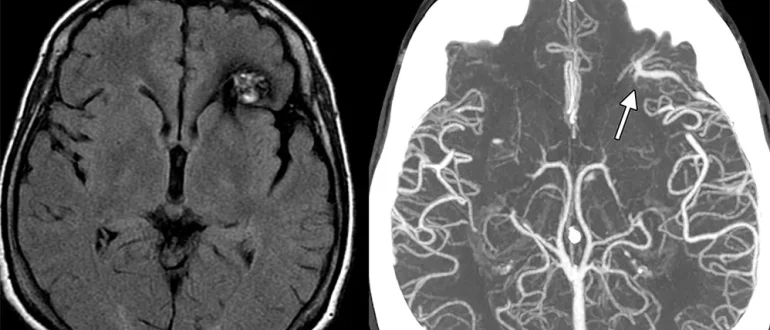

Что такое кавернома головного мозга Кавернома (кавернозная ангиома) головного мозга — это сосудистая мальформация, представляющая собой скопление патологически изменённых кровеносных сосудов. Эти сосуды образуют полости («каверны»), заполненные кровью,…